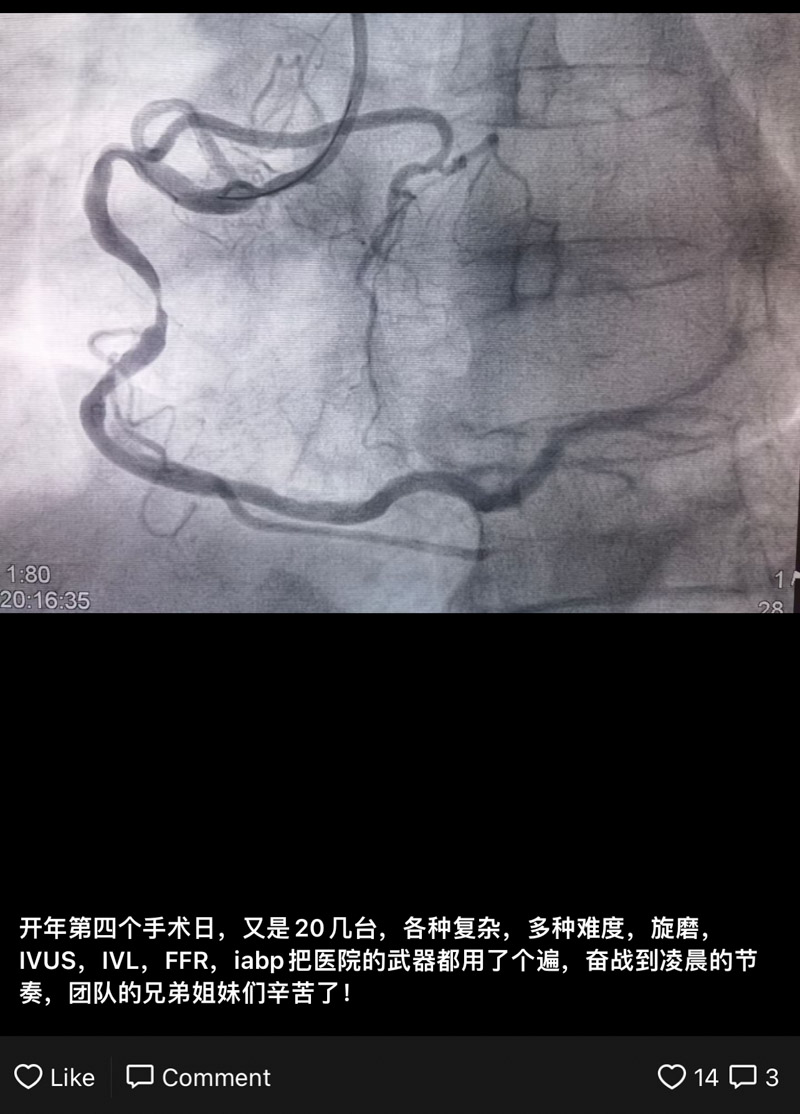

“開年第四個(gè)手術(shù)日,又是20幾臺(tái),各種復(fù)雜、多種難度,旋磨、IVUS、IVL、FFR、IABP把醫(yī)院的武器都用了個(gè)遍,奮戰(zhàn)到凌晨的節(jié)奏,團(tuán)隊(duì)的兄弟姐妹們辛苦了!”柳州市人民醫(yī)院心血管內(nèi)科副主任王勇發(fā)了這樣一條朋友圈。雖然辛苦,但團(tuán)隊(duì)每一個(gè)人都無(wú)怨無(wú)悔,和死神進(jìn)行著一場(chǎng)場(chǎng)較量!